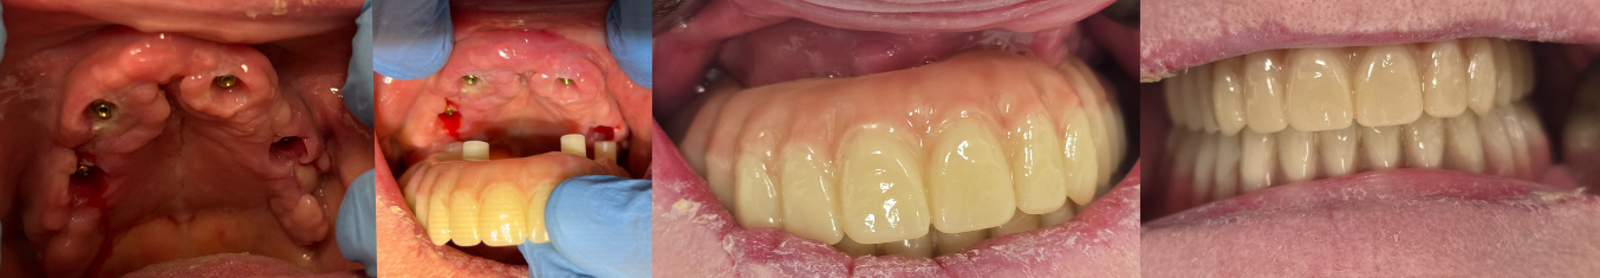

Een 80-jarige patiënte, bekend met gebruik van bloedverdunners, presenteerde zich met functionele en esthetische klachten door volledig uitneembare prothesen in boven- en onderkaak die zij al >40 jaar droeg. De prothesetanden waren sterk versleten en zowel retentie als stabiliteit was matig, wat leidde tot kauwproblemen en verminderd comfort. Klinisch en radiologisch werd een zeer ernstige resorptie vastgesteld in zowel de maxilla als de mandibula, passend bij Cawood & Howell-classificatie V–VI (figuur 9-11).

Preoperatieve situatie op een OPT.

Klinische preoperatieve situatie.

CBCT-scan preoperatief.

De genezingsfase verliep ongecompliceerd met behoud van stabiliteit en goede weefseladaptatie. Na vier maanden werd een definitieve, vastgeschroefde brug geplaatst (figuur 16). Hiermee werd een stabiele, functionele en esthetische vaste rehabilitatie bereikt, passend bij de behandelwens van de patiënte en met ondanks de ernstige atrofie minimale chirurgische morbiditeit.

Plaatsen van de vaste brug en genezing van de implantaten.